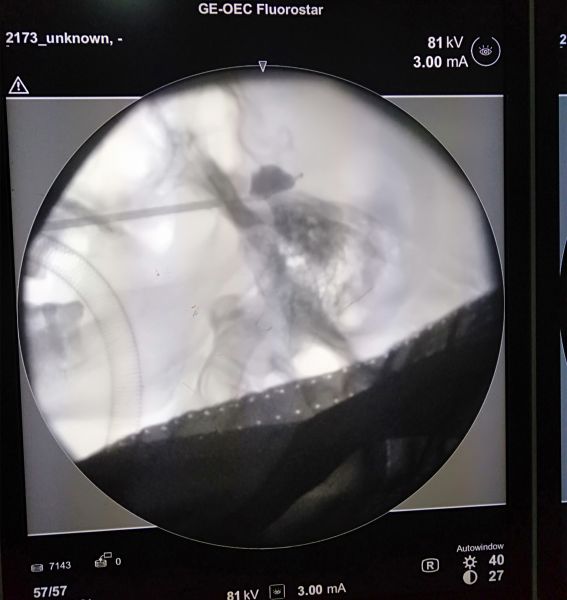

球囊扩张中造影剂透视呈鸭梨图像

术中麻醉医师根据都女士的身体状况为其制定了精准麻醉方案,顺利为患者实施全身麻醉并保障了整个手术过程的安全。接下来手术团队精准定位并穿刺卵圆孔,经穿刺针将球囊导管置入三叉神经半月节区域,此时将造影剂注入球囊中,在C型臂透视下,球囊充盈至“梨形”。球囊压迫3 分钟左右,压迫完成后将造影剂抽出,拔除穿刺针及球囊导管。几分钟后患者苏醒,疼痛消失,观察24小时,疼痛无反复,患者顺利康复出院。